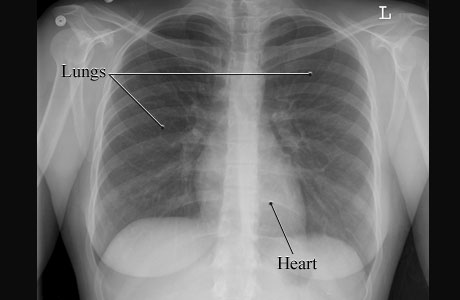

X-Ray of a Normal ChestCourtesy of Intermountain Medical Imaging, Boise,

Idaho. This is a picture of a normal chest X-ray of a woman showing the

air-filled spaces of the lungs and the more solid gray shape of the heart. The

lungs and heart are normal in size and shape. ByHealthwise Staff Primary Medical ReviewerAdam Husney, MD - Family Medicine Specialist Medical ReviewerHoward Schaff, MD - Diagnostic Radiology Current as ofOctober 14, 2016 Current as of: